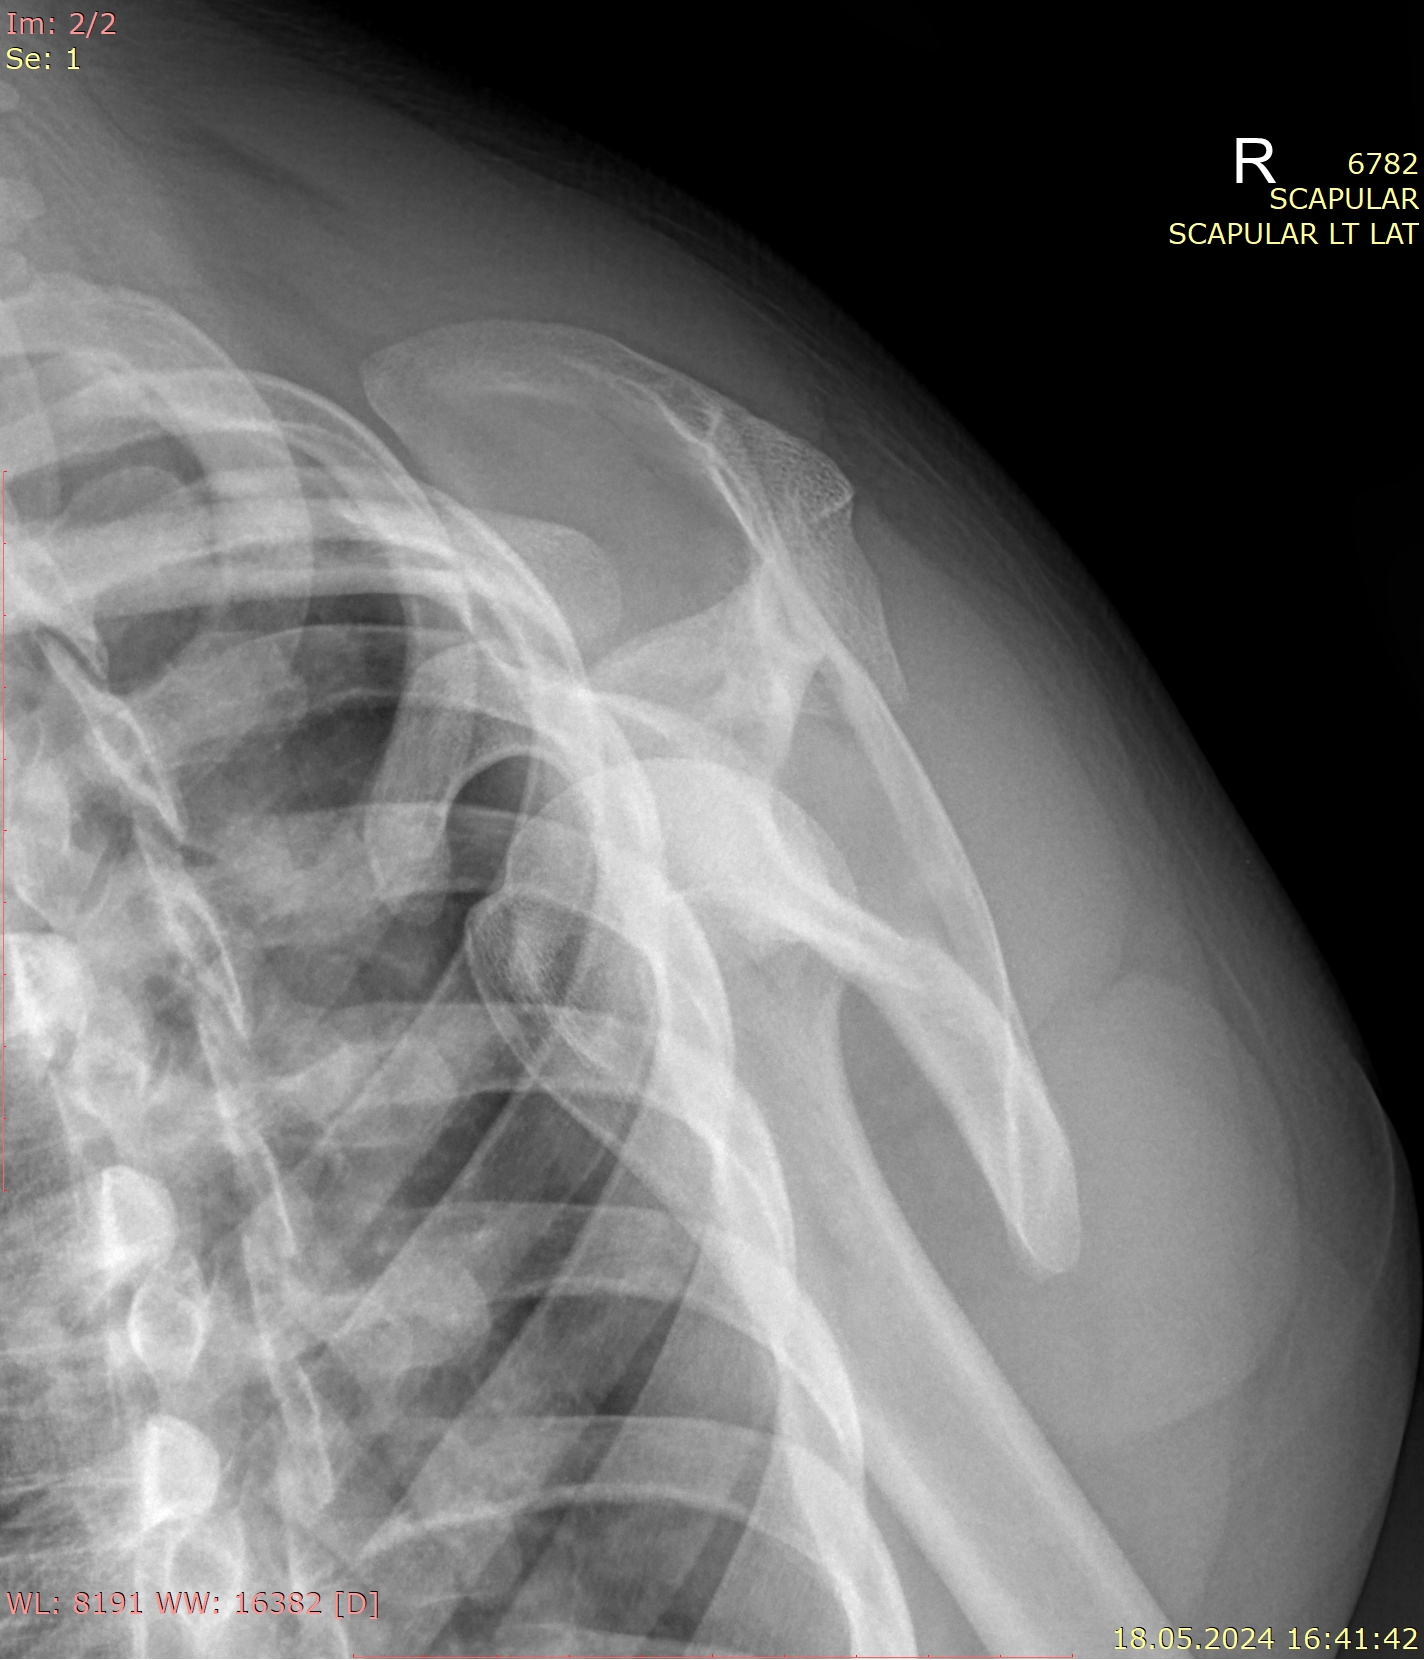

Лопатка ― плоская парная кость, играющая важную роль в креплении верхней конечности к туловищу. При патологиях лопатки, как и любой другой кости, в качестве первичного исследования используют рентгенографию. Этот метод исследования основан на способности органов по-разному поглощать рентгеновское излучение. Костная ткань, как наиболее плотное образование тела, поглощает больше всего х-лучей и на снимке кости выглядят светлыми.. Линии переломов выглядят темными трещинами, а новообразования имеют отличную от нормальной структуру.

• Состояние костной ткани лопатки: перелом, новообразования, очаги некроза;

• Местоположение лопатки относительно других костей;

• Состояние суставных щелей сочленений, попавших на снимок;

• Состояние мягких тканей, инородные тела.